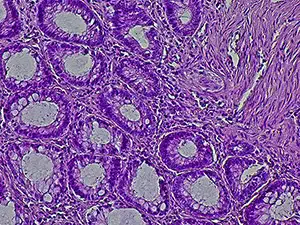

Primarily caused by human papilloma virus infection, SCAC is the most common form of anal cancer. According to federal statistics, it was estimated that 10,930 individuals would be diagnosed with anal cancer and approximately 2,030 patients would die of the disease in the United States in 2025.